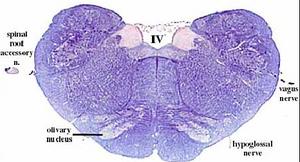

secciones transversales a diferentes niveles del tronco del encéfalo mostrando la localización de los núcleos neuronales eferentes de los nervios craneales

EFERENTES:

somatoeferentes (SE) : inervan músculos esqueléticos

visceroeferentes(VE): parasimpáticos